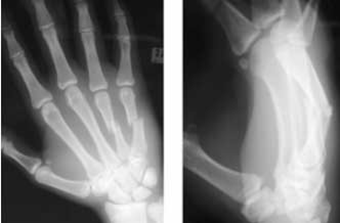

Describe the fracture

Displaced, dorsally angulated transverse fractures of the metacarpal shafts of the ring and small fingers.